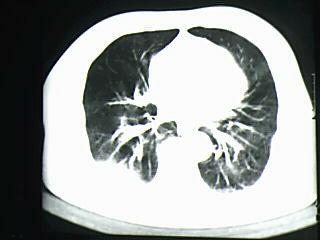

标题: CT19768:男 61岁 胸痛 咯血 一周。无发烧、无结核病史。 [打印本页]

标题: CT19768:男 61岁 胸痛 咯血 一周。无发烧、无结核病史。

右下肺中心型肺癌

右下肺支气管扩张

纵隔窗图像不佳,怀疑右下叶支气管有狭窄,来几张清楚的,暂考虑----感染性病变----抗炎后复查

考虑 右下肺感染性病变,建议抗炎后复查。

考虑右肺下叶感染性病变;建议抗炎治疗后复查。